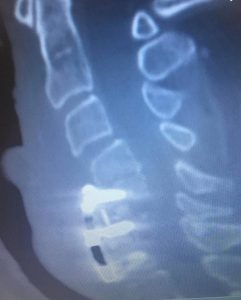

Here is an extreme example of a patient who came to me for correction of a previous attempt at surgery which failed to correct her severe Kyphosis and spinal cord compression. After the much more extensive surgery that I performed, she began to recover strength in her arms again and her ability to walk improved.